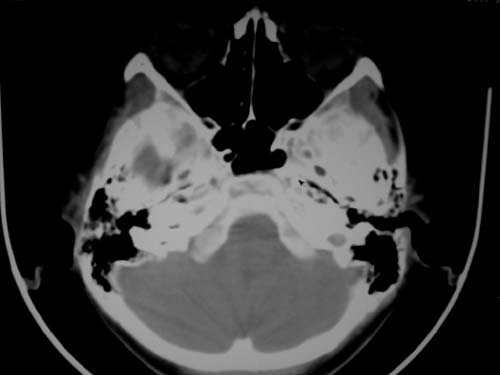

标题: CT19740:女,12岁,鼻塞,流黄鼻涕。 [打印本页]

标题: CT19740:女,12岁,鼻塞,流黄鼻涕。

双侧上颌窦炎,增殖腺肥大。

1)双侧上颌窦炎。2)鼻咽腺样体肥大。